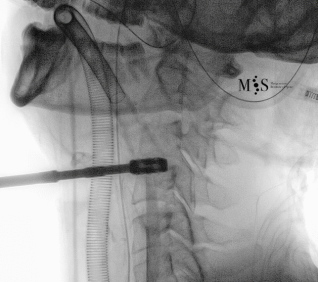

Images showing the endoscopic placement of a cage into a cervical disk

Animated image showing the endoscopic insertion of an intervertebral cage into a cervical disk.

Note the distraction of the disk space during as the cage is inserted.

Endoscopic ACDF starts with an endoscopic discectomy to decompress neural structures, like the spinal cord, and prepare the disk for the cage placement. Once the interbody cervical disk has been prepared, the an interbody device is percutaneously placed into the disk. This device can either be a titanium interbody cage to achieve vertebral fusion or a disk prothesis that allows to restore movement in the cervical spine. The placement of the device is done unter x-ray fluoroscopic control and direct endoscopic vision, see the animation on the figure at the right side of this page.